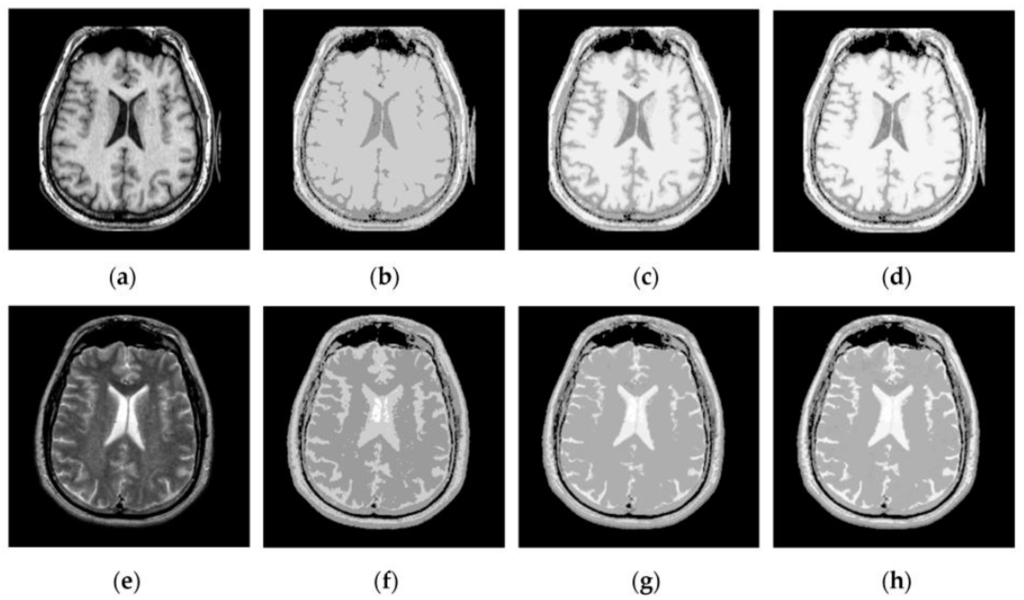

4.2. Visual Comparisons of Fused Results